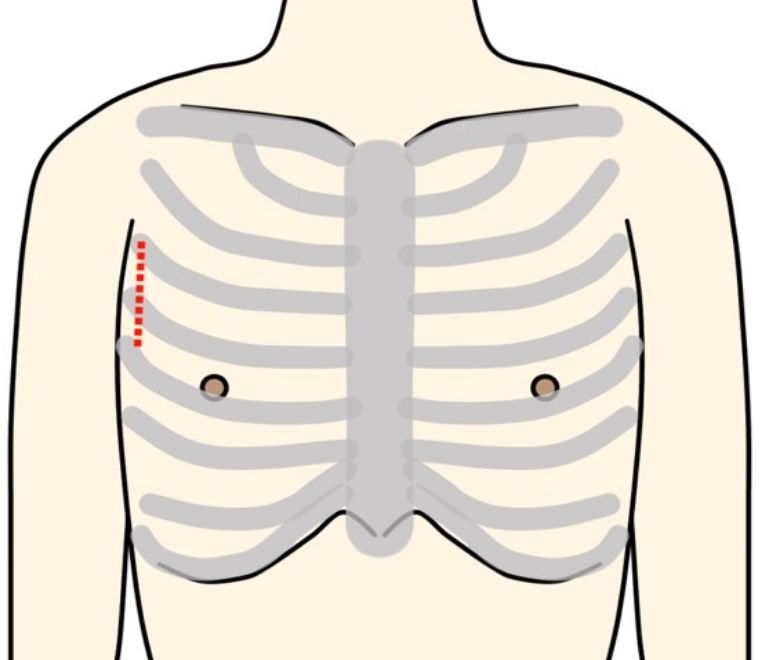

主に一箇所のバイパスを行う場合に有用な方法です。小さい傷で行う場合、内胸動脈を採取が困難となる問題があります。カメラを用いない直視法では、視野が悪い為、傷が大きくなりさらに肋骨の間を器具で大きく広げるために、疼痛や美容的な問題があります。3D内視では広い範囲の動脈を小さい傷で採取できる為、これらの問題を解決できる利点があります。ただし、内視鏡採取は豊富な経験が必要な為、全国的にも限られた施設でしか行っておりません。

吻合は傷を痛めないように組織に優しい器具を用いて行います。

この方法を基本として、複数の血管へのバイパス手術を行っています。

Off-Pump CABGは脳硬塞の発生や腎臓機能の悪化などの合併症が少なく、心臓を停止しないため心臓や全身への負担も少なくなります。日本全体では50%ほどの割合で人工心肺が使用されておりますが、当院では人工心肺の影響を考慮し、ほぼ全例にOff-Pump CABGで行っております。現在はOff-Pump CABGに加えて、「左小開胸によるバイパス術(MIDCAB)」も行っております。